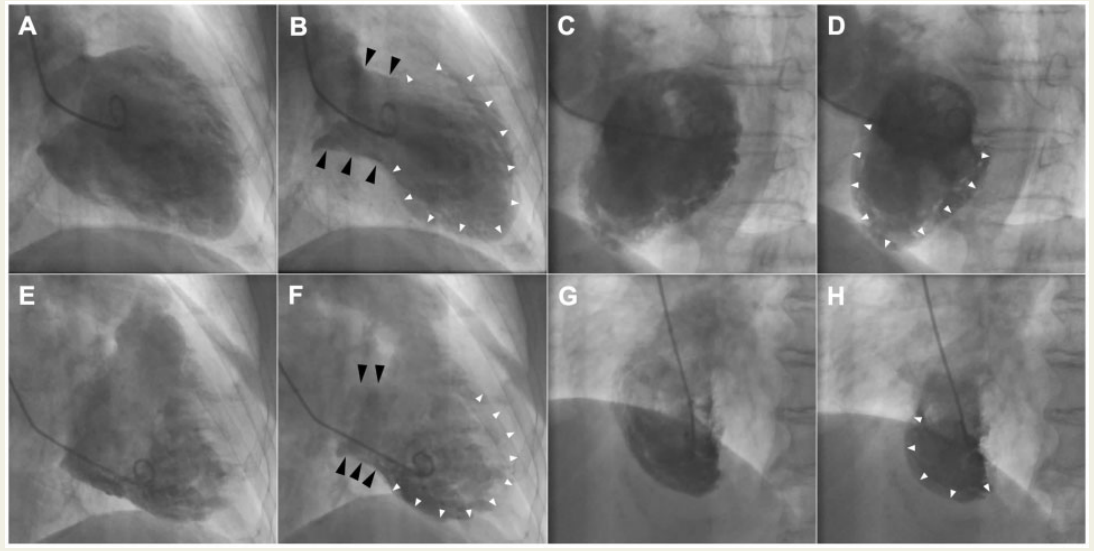

左心室造影显示,基底节段高动力(黑色箭头),左心室中段至顶端气球样向外膨出(白色箭头),超出单个心外膜冠状动脉的范围[右前斜位 (RAO)投影:A(舒张)和B(收缩);左前斜位(LAO):C(舒张)和D(收缩)]。

此外,右心室造影显示,基底部过度收缩,中段至顶端气球样向外膨出(白色箭头),尤其是三尖瓣下,右心室节段(黑色箭头)[RAO投影:E(舒张)和F(收缩);LAO:G(舒张)和H(收缩)]。